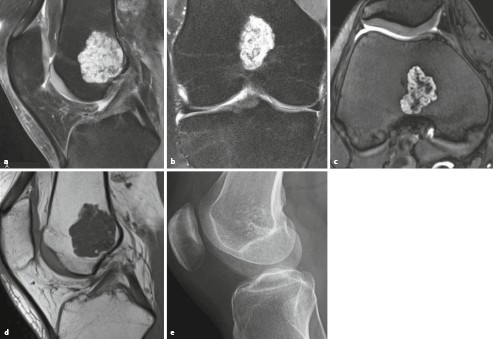

Primare Und Sekundare Knochengeschwulste Springerlink